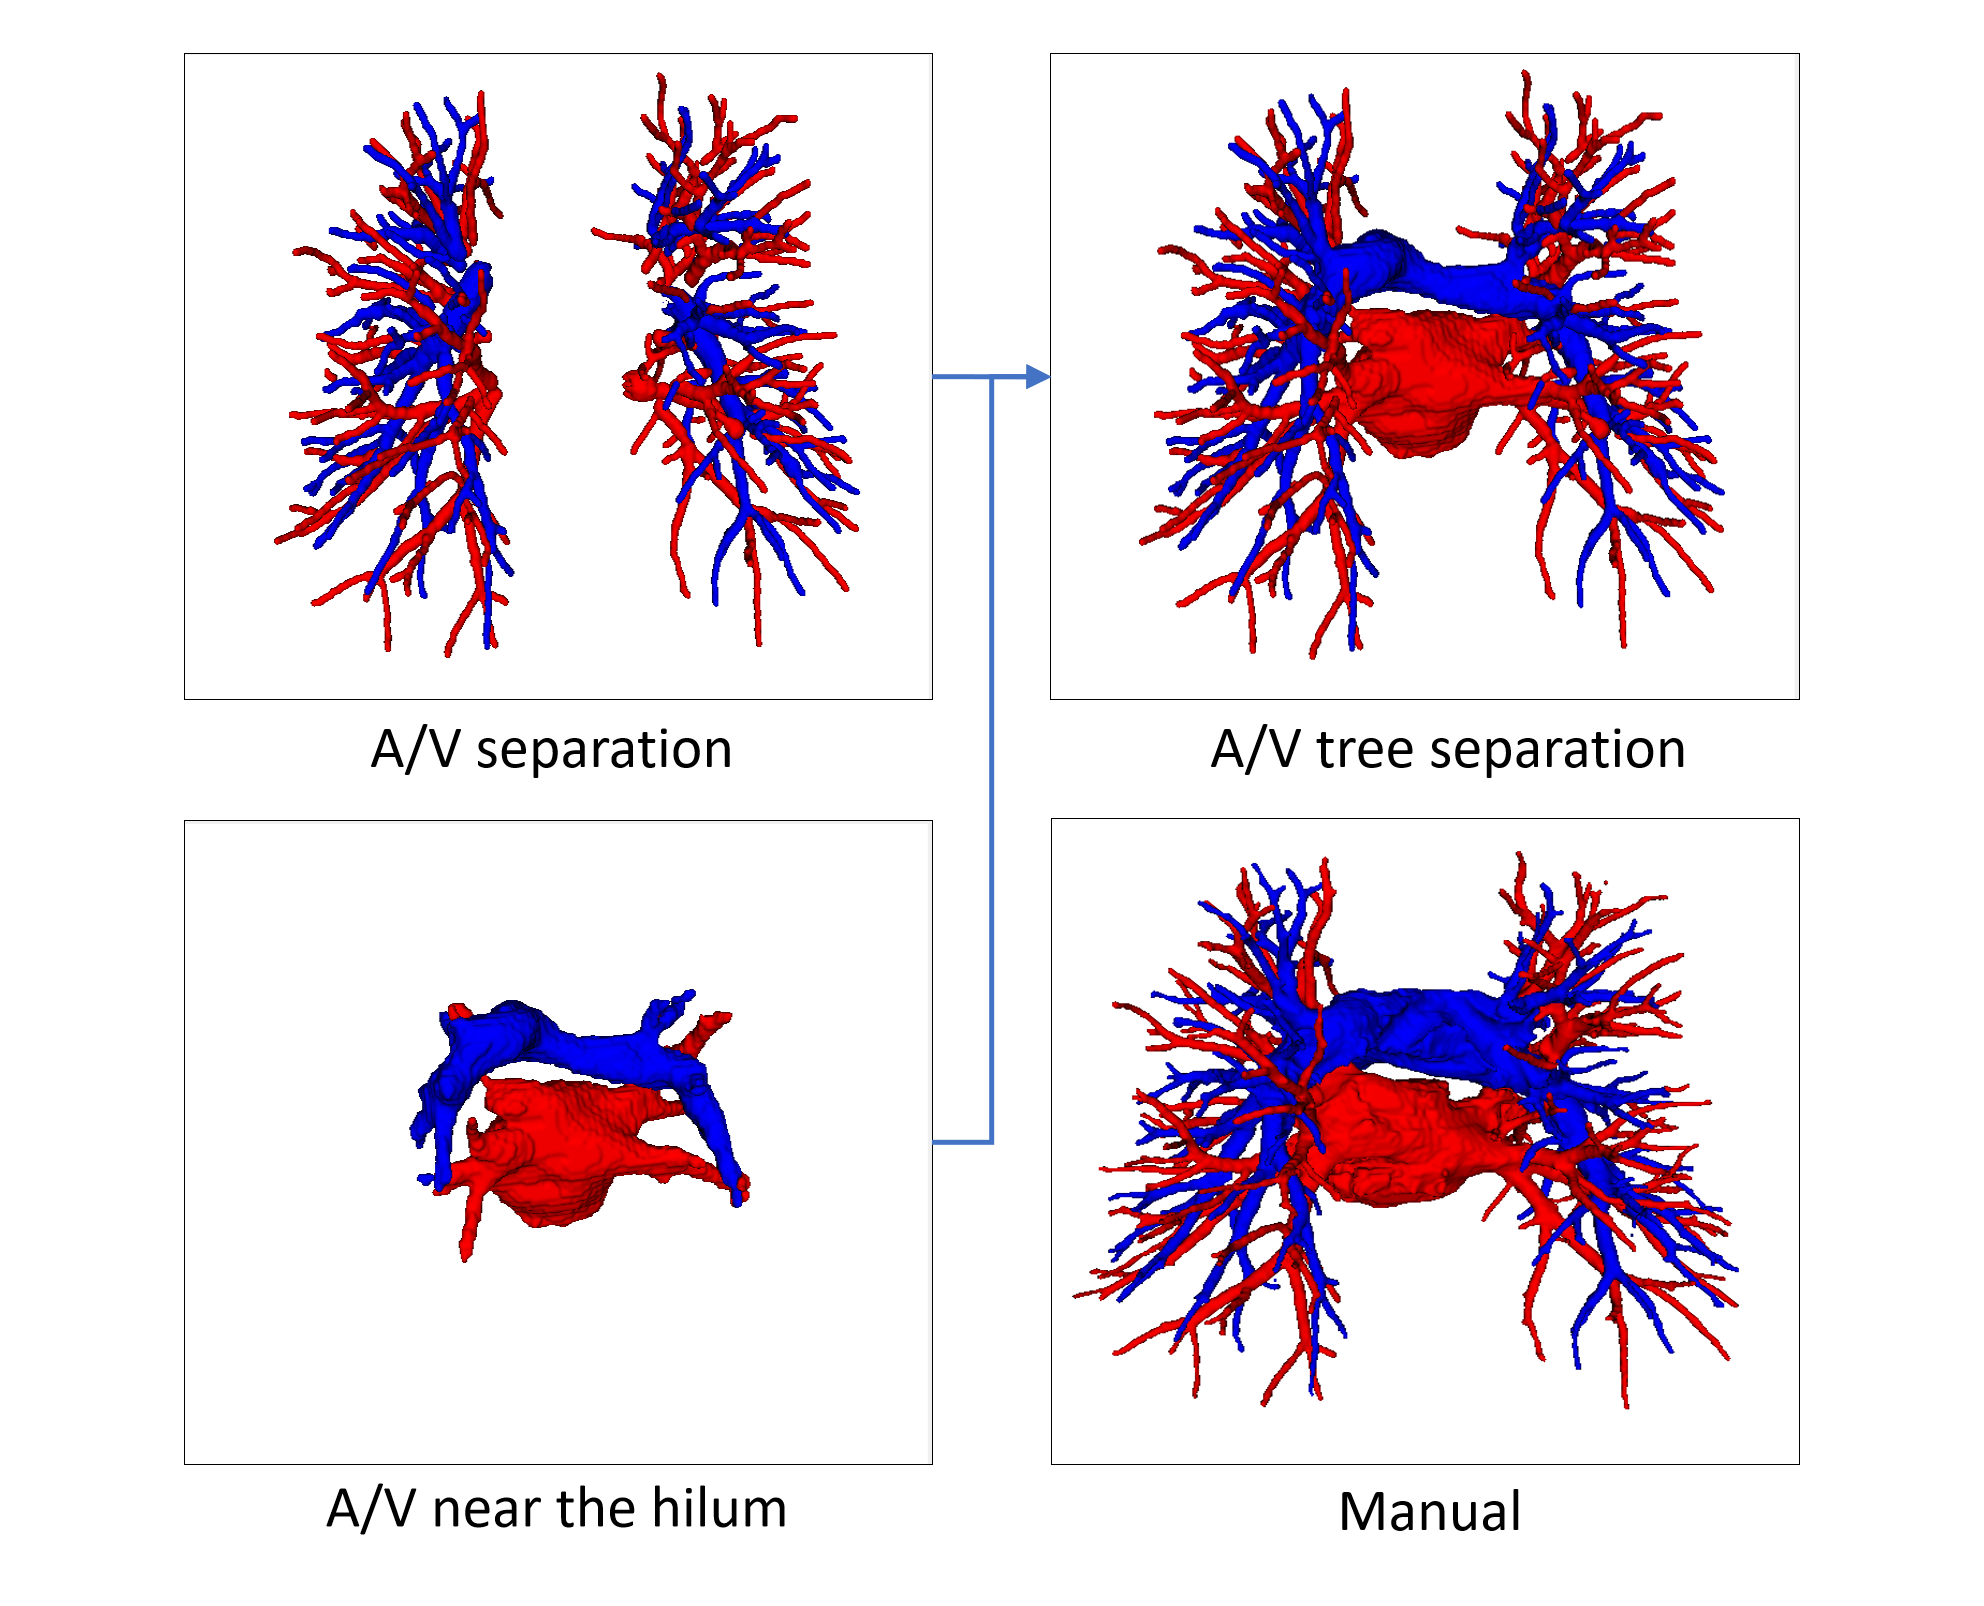

In order to reconstruct pulmonary A/V, base on the refined prediction and scale of center voxels, each voxel in the scale region is labeled with the corresponding prediction of center voxels. It is then fused with vessels near the hilum of the lung for final A/V results.

Our evaluation method for A/V separation is based on topological particles rather than voxel classification. This finding is mainly due to the difficulty of obtaining accurate annotations of pulmonary vessels based on voxel levels, which are also indistinguishable by doctors. In addition, in clinical practice, doctors focus more on the structural branching direction of vessels, consistent with the evaluation system based on topological particles. A/V separation can provide effective information for doctors to make surgical plans and perform surgical navigation, and proximal vascular extension can help doctors to locate the vessel more quickly. Therefore, the final A/V separation results include vessels close to the hilum of the lung, as shown in Fig. 12. Our evaluation system for the method of A/V separation do not include vessels near the hilum of the lung mainly because the vessels near the hilum are abnormally large and nontubular, and the vascular topology could not be extracted.

Fig. 16 shows the final separation result of our method at the intersections of the arteries and veins. The proposed topology optimizer considers the interbranch and intrabranch relationships. The extracted topological subtree is used to maintain the spatial connectivity of topological particles. The branch confidence calculated using topological branches is used to correct the topological subtree. To some extent, our method can solve the misclassification problem caused by interlaced arteries and veins.